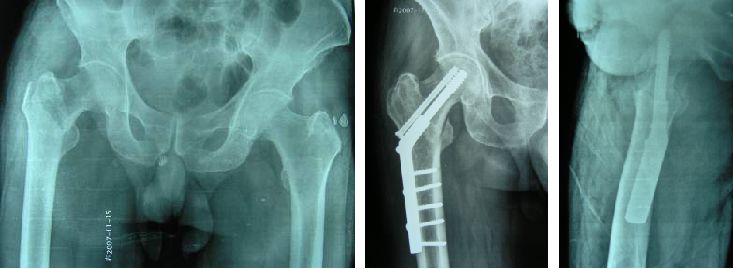

В анамнезе очевидная травма, боль в пораженной конечности и ограничение движений.Отмечается укорочение и наружная ротационная деформация нижней конечности до 90°.Для установления диагноза часто требуется рентгенологическое исследование, а типирование основывается на рентгенограммах.Симптомы межвертельного перелома аналогичны симптомам перелома шейки бедренной кости, но последний менее выражен, чем первый, с точки зрения локальной боли, отека, потери функции и укорочения пораженной конечности, а пораженная конечность в основном имеет легкую форму тазобедренного сустава. сгибание и сгибание колена и деформация наружной ротации, обычно между 45°-60°.

Переломы АО и Эванса-Дженсена являются двумя наиболее часто используемыми типами переломов, и из этих двух наиболее распространенным является тип перелома АО.

Тип I: Простой межвертельный перелом с уклоном линии перелома сверху вниз, без смещения и стабильности.

Тип II: Смещение сочетается с отрывным переломом малого ротора, но бедренная шпора цела (бедренная шпора представляет собой плотную костную пластинку, расположенную глубоко внутри места соединения шейки бедренной кости с телом малого ротора.

Тип III: Сочетанный перелом большого вертела с скоплением переломов бедренной шпоры, со смещением, чаще с задним межроторным переломом.

Тип IV: Трехфрагментарный перелом в сочетании с оскольчатым переломом малого вертела, который может проявляться взрывным переломом шейки бедра и коронковой поверхности большого вертела.

Тип V: заднелатеральный и медиальный безопорный перелом (сочетание типов III и IV).

Тип Р: передний межвертельный перелом с косой линией перелома от верхней медиальной к нижней латеральной, что может быть связано с небольшим переломом ротора и разрушением бедренной ости.